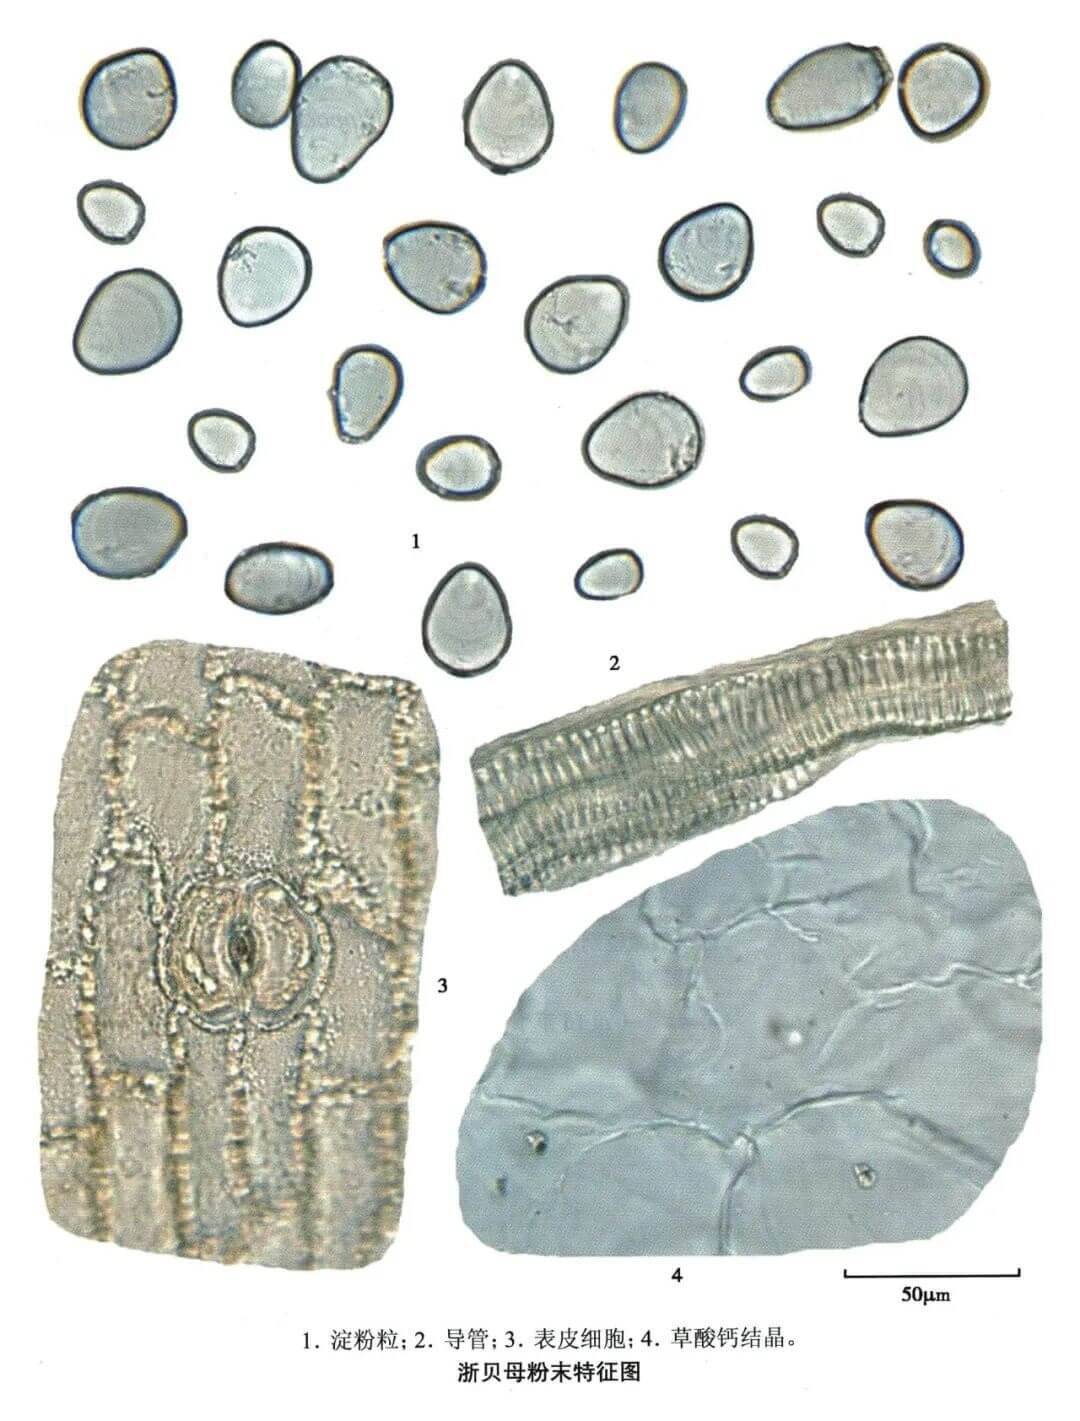

浙贝母

| 浙贝母 |

|---|

| 【参考标准】 《中国药典》2020年版一部 |

| 【显微鉴别】 本品粉末淡黄白色。淀粉粒甚多,单粒卵形、广卵形或椭圆形,直径6~56μm,层纹不明显。表皮细胞类多角形或长方形,垂周壁连珠状增厚;气孔少见,副卫细胞4~5个。草酸钙结晶少见,细小,多呈颗粒状,有的呈梭形、方形或细杆状。导管多为螺纹,直径至18μm。 |

| 【显微重点】 淀粉粒;表皮细胞及草酸钙结晶较难发现。 |

| 【图谱来源】 《中药成方制剂显微图典》 |